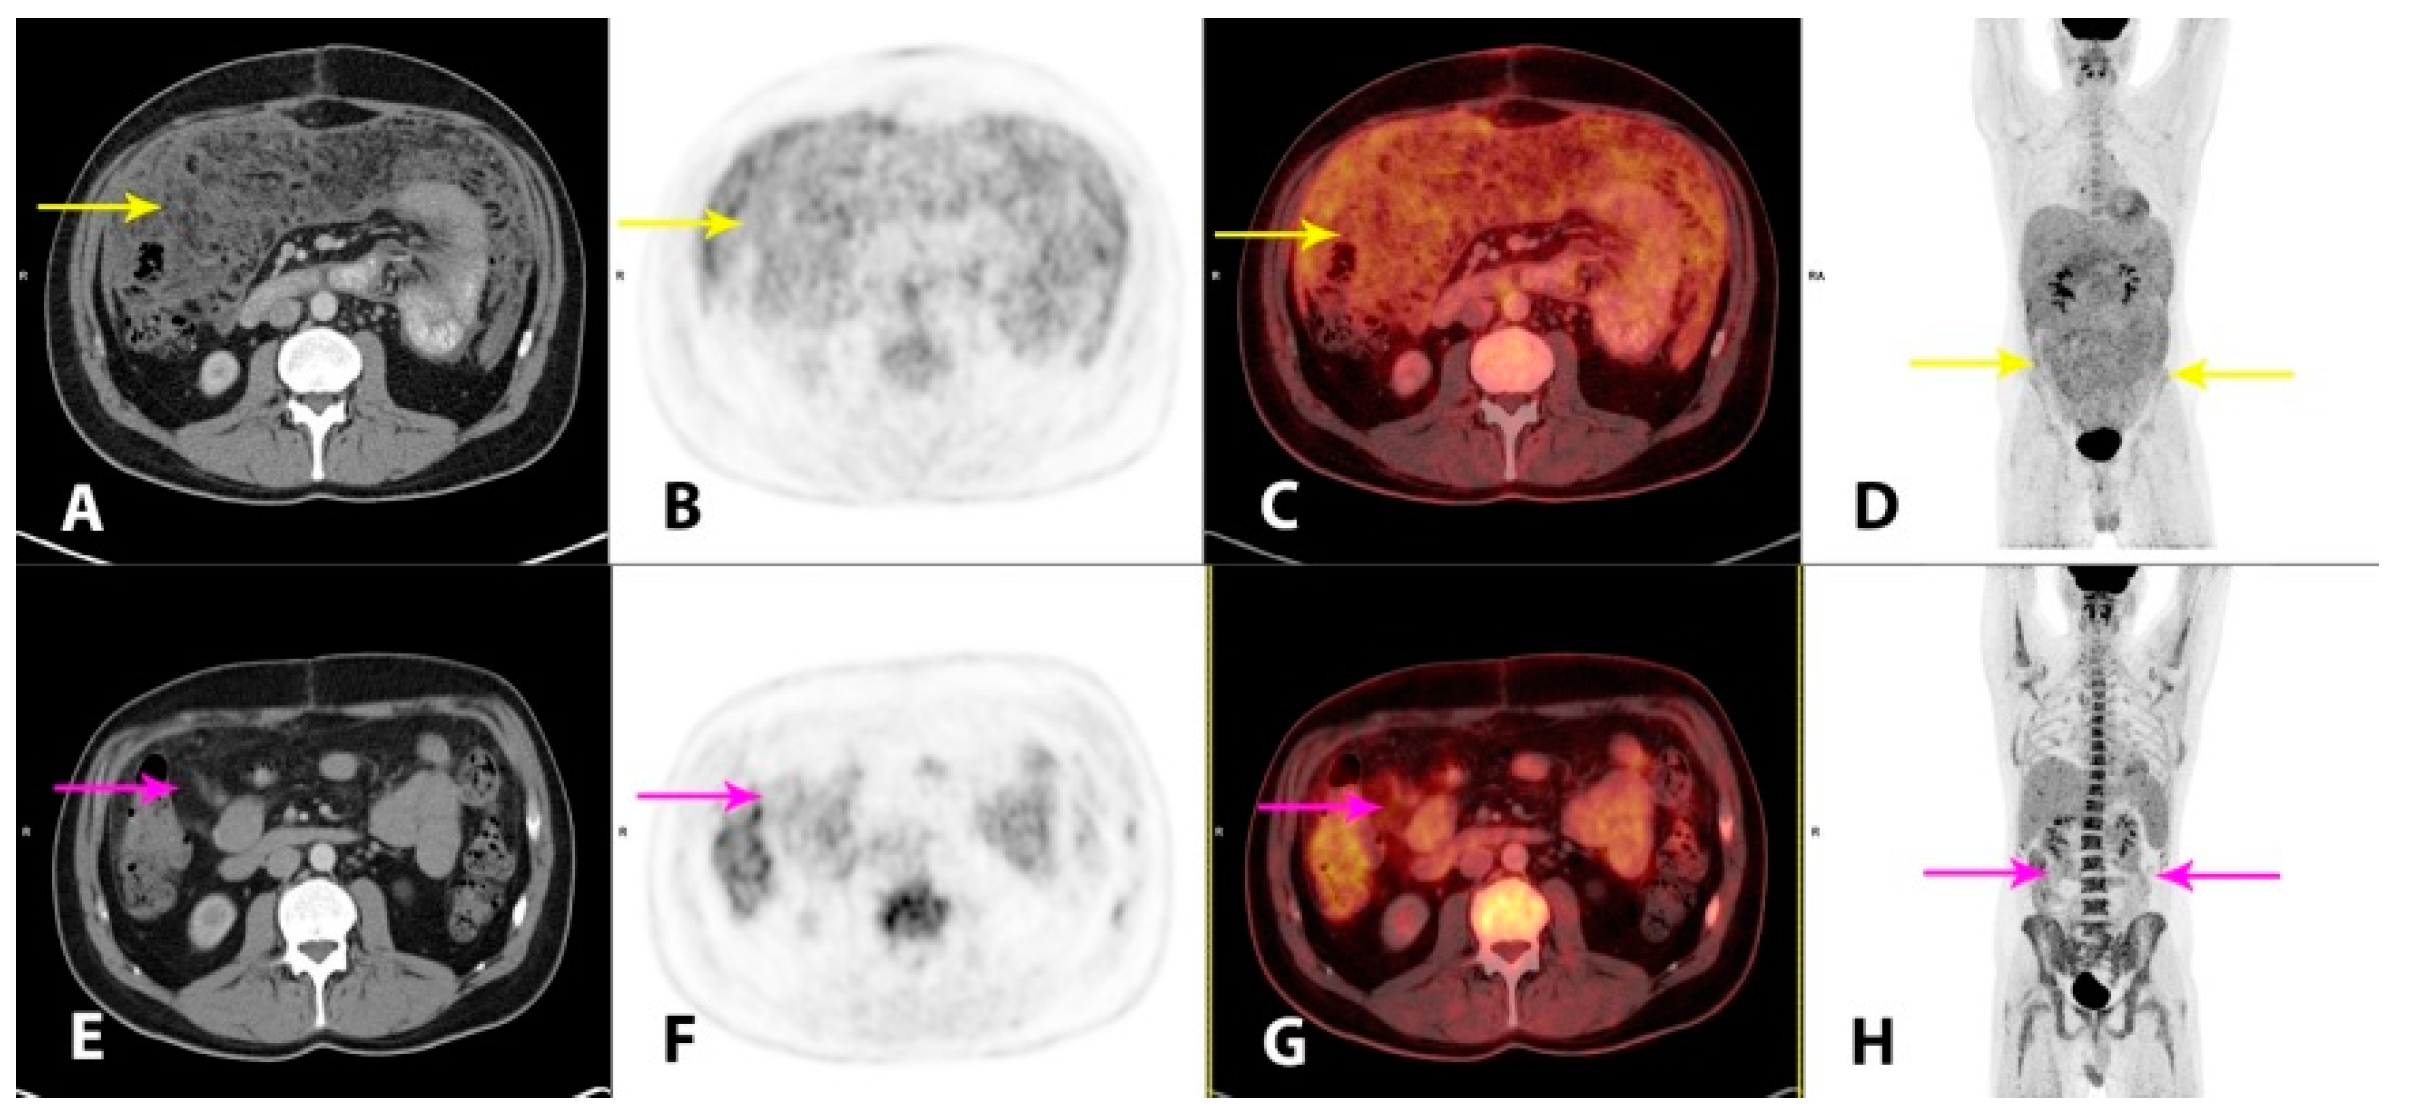

Figure 3. Hybrid imaging with 2-deoxy-2-[18F]fluoro-D-glucose positron emission tomography/CT (2-[18F]FDG PET/CT) was performed for the staging of the disease and as baseline for monitoring of the treatment response. Imaging performed 1 h post-injection of 4.0 MBq/kg 2-[18F]FDG showed a moderately metabolically active, irregular thickening of the peritoneal folds and extensive carcinomatosis-like infiltration in the omentum, mesentery and the pelvic cavity (AD, yellow arrows). There was minor ascitic fluid in the abdominal and pelvic cavities. There were also metabolically active, enlarged lymph nodes in the mediastinum and upper retroperitoneum. The findings were considered highly suspicious for malignancy. At this point, plasma lactate dehydrogenase (LDH) levels, a future tumor marker in this patient, were elevated (366 U/L; reference range 105–205 U/L). An initial steroid treatment with prednisolone 100 mg/daily had a good effect on the tendency of the recollection of ascites. However, as no standardized treatment for this patient category without comorbidity exists, a hematological specialized tumor board, after consent from the patient, decided to administer a chemotherapy regimen of ifosfamide, carboplatin and etoposide (ICE), which was initiated one month after initial hospitalization. The patient tolerated the treatment well. At clinical follow-up after two cycles of ICE, the patient’s wellbeing was improved, the plasma LDH was normalized and imaging with 2-[18F]FDG PET/CT demonstrated a substantial partial response (PR), both metabolically and morphologically, of the previously described findings in the peritoneum. There were still metabolically active, carcinomatosis-like findings in the omentum, mesentery and on the liver surface (EH, magenta arrows). There were no pathological lymph nodes. After completion of four cycles of ICE, the metabolic complete response (CR) and a further morphological PR were reported on follow-up 2-[18F]FDG PET/CT (not shown). The plasma LDH was still within a normal range. The patient tolerated the fifth and final cycle of ICE well.